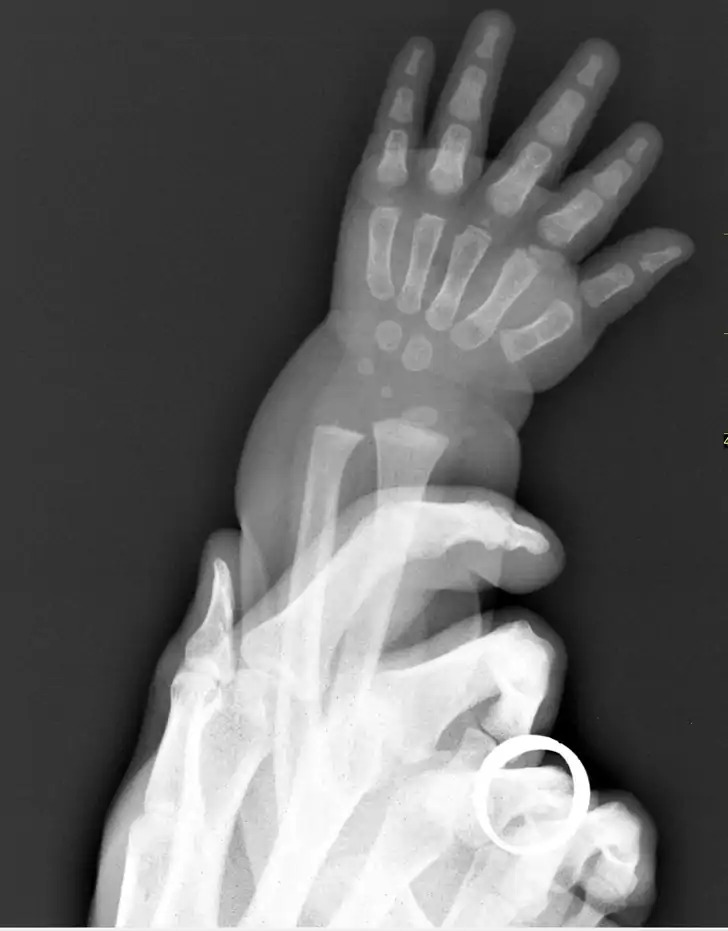

2. Snímka detskej ruky v porovnaní s rukou dospelého človeka